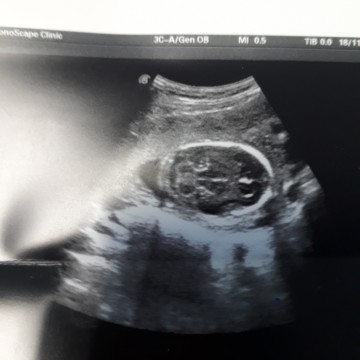

ลูกคนที่สอง คุณหมอบอกว่าหัวน้องยาวผิดปกติ แต่ซาวกี่รอบก็ทรงเดิม คุณหมอบอกว่า ร่างกายของน้องปกติดี มีอวัยวะครบสมบูรณ์ ตรวจดูไขสันหลังของน้องก็ปกติ แต่ทรงศีรษะของน้องจะเป็นแบบนี้จนโต ทารกปกติจะหัวกลมๆ ลูกเรานี้แบนเลย เครียดมาก กังวลมากด้วย กลัวออกมาไม่ปกติ เหมือนเด็กคนอื่น